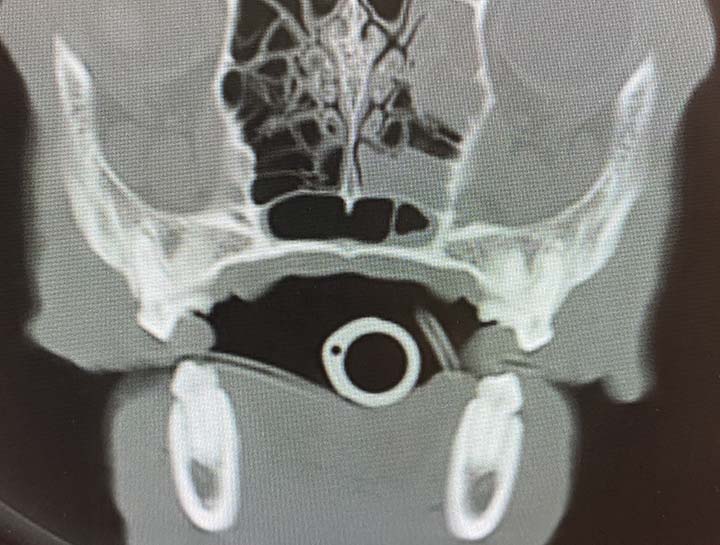

Computerized Tomography (CT)

Advanced imaging to determine underlying issues.